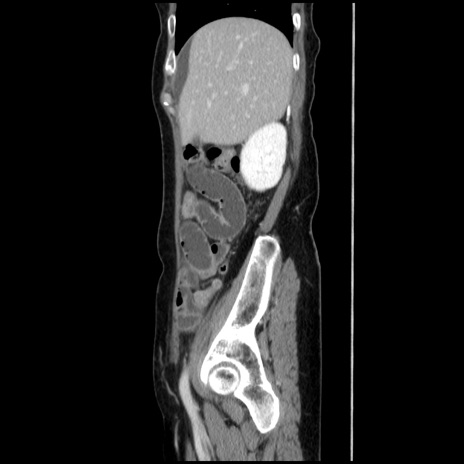

症例32(矢状断像)

【症例】40歳代 女性

【主訴】上腹部痛、嘔気・嘔吐

【現病歴】約9時間前頃から急に上腹部痛、嘔気、嘔吐が出現。改善しないため救急要請。

【既往歴】子宮頚癌(広汎子宮全摘術、放射線療法)、腸閉塞

【身体所見】腹部:平坦、軟、腸雑音亢進、上腹部を中心に腹部全体に圧痛あり。

【データ】WBC 8400、CRP 0.03